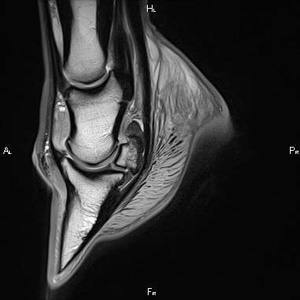

MR

Az MRI (Magnetic Resonance Intake) vizsgálat hátterének elmagyarázását nem merném vállalni. A meglehetősen mély fizikai ismeretekre épülő szerkezet a mai legmodernebb képalkotó vizsgálati módszer. A CT-hez hasonlóan felszeleteli képeivel a vizsgált testtájékot, de a különböző szövetek mind élethűen megjelennek rajta. A CT-nél még érzékenyebb, ráadásul az aktív folyamatokat is megjeleníti. Rendkívül részletes! Hátránya, hogy egyelőre egy teljes ló nem fér be, csak könyékig, térdig tudjuk használni. Legtöbb hasznát a pata szarutokján belüli képletek vizsgálatánál, illetve a csontok belsejében zajló folyamatok leképezésénél vesszük.

Lélegzetelállítóan szép kép a patáról